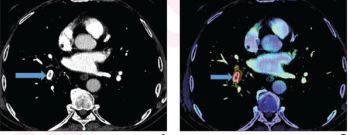

The artificial intelligence (AI)-powered Neuro Suite reportedly enables radiologists to access leading neurological AI algorithm solutions in the field, including the brain magnetic resonance imaging (MRI) segmentation capabilities of the Combinostics’ algorithm that can help differentiate degenerative pathologies such as Alzheimer’s disease and dementia.